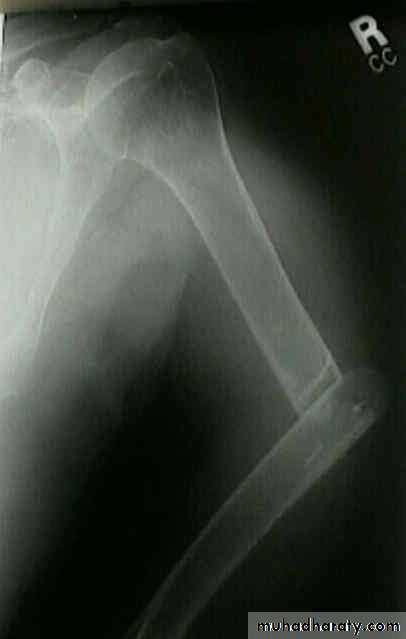

40 years male fall on out streched hand

Radial nerve palsy after reduction